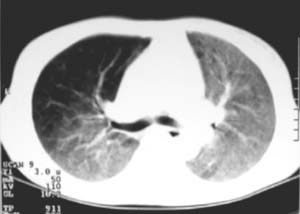

以下是引用zjzjr在2007-9-20 12:29:00的发言:[br]双肺磨玻璃改变,考虑肺水肿.

以下是引用yangzongshan在2007-9-20 18:29:00的发言:[br]两肺毛玻璃样改变,其内可见肺纹理影,无胸腔积液,故考虑肺泡蛋白沉积症

以下是引用276894491在2007-9-20 13:40:00的发言:[br]考虑肺水肿;外源性过敏性肺炎不排除。

以下是引用逸风在2007-9-20 20:45:00的发言:[br]两肺磨玻璃样改变,临床病史短,发热,考虑病毒感染合并右肺代偿性肺气肿.待排肺水肿,病史短,不支持肺泡蛋白沉着症.